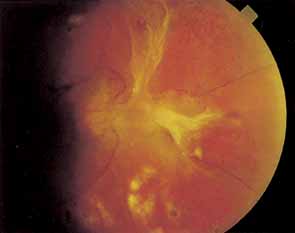

Although the macular edema, exudates, and capillary occlusions seen in NPDR often cause legal blindness, affected patients usually maintain at least ambulatory vision. PDR, on the other hand, often results in severe vitreous hemorrhage or retinal detachment with hand-movements vision or worse. It has long been assumed that sudden vitreous contractions tear the fragile new vessels, causing vitreous hemorrhage. However, 62% to 83% of diabetic vitreous hemorrhages occur during sleep,16,17 possibly because of an increase in blood pressure secondary to early morning hypoglycemia or to rapid eye movement (REM) sleep. Because so few hemorrhages occur during exercise, we do not restrict the activity of patients with proliferative retinopathy. The location of the hemorrhage is important in predicting whether it will clear on its own. If blood is behind the posterior vitreous face it is likely to settle to the bottom of the eye and be absorbed. However, when hemorrhage breaks into formed vitreous it is less likely to clear spontaneously.

A large superficial hemorrhage may separate the internal limiting membrane from the rest of the retina. Such hemorrhages usually are round or oval but may also be boat-shaped (Fig. 12). The blood may remain confined between the internal limiting membrane and the underlying retina for weeks or months before breaking into the vitreous. Subinternal limiting membrane hemorrhages were formerly thought to lie between the internal limiting membrane and the cortical vitreous and were called subhyaloid or preretinal hemorrhages. It is now felt that true subhyaloid hemorrhages are probably quite rare. Tight subinternal limiting membrane hemorrhages are dangerous beause they may progress to traction retinal detachment.18,19

Fig. 12 Subinternal limiting membrane hemorrhages.